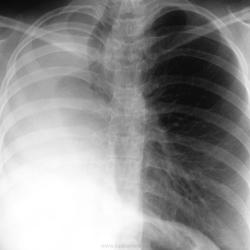

Лучевая диагностика туберкулеза сегодня

Я.В. Лазарева, Г.В. Ратобыльский, Е.В. Серова, М.Б. Мальсагов

НИИ фтизиопульмонологиии ММА им. И.М. Сеченова